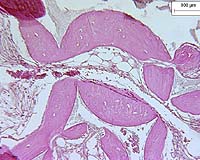

File image.

The experiments were done using mouse mammary and fibroblast cells. The researchers used three different processes for reprogramming the cells to a "stem," or embryonic, state. The first method was developed expressly for this study, and the others have already been well documented.